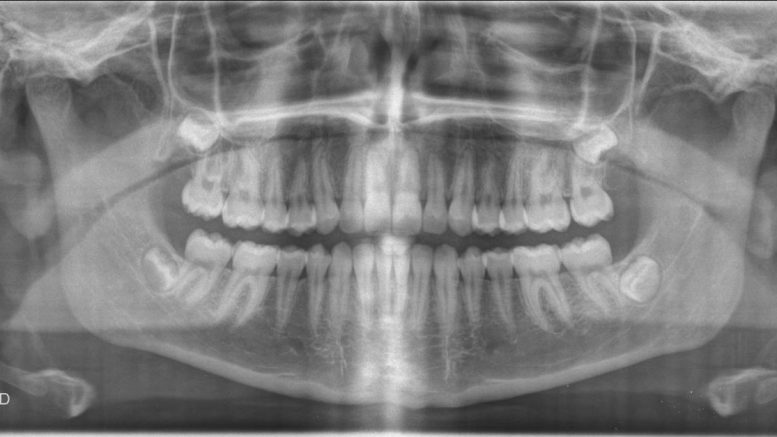

Si vous désirez passer votre examen d’imagerie dentaire dans un centre de radiologie de qualité, vous ne devez pas hésiter à faire confiance à l’ACRIM. L’ACRIM est un centre d’imagerie médicale qui possède cinq sites sur Senlis, Crépy-en-Valois, Noyon, Saint Côme et Compiègne. Ainsi, si vous vivez dans ces communes ou dans les alentours, vous pourrez prendre rendez-vous avec ces professionnels afin de passer votre examen dentaire. Vous bénéficierez du meilleur matériel de pointe en matière d’imagerie dentaire et médicale en recevant rapidement vos résultats. Vous pourrez y passer différents examens dentaires comme : le panoramique, ou encore le télécrâne mais aussi le Cone Beam. Grâce à ces examens d’imagerie dentaire, votre dentiste pourra détecter rapidement une infection, ou un problème au niveau de votre dentition ou de vos mâchoires. Vous bénéficierez du meilleur suivi grâce à des radiologues compétents et possédant de nombreuses années d’expérience.